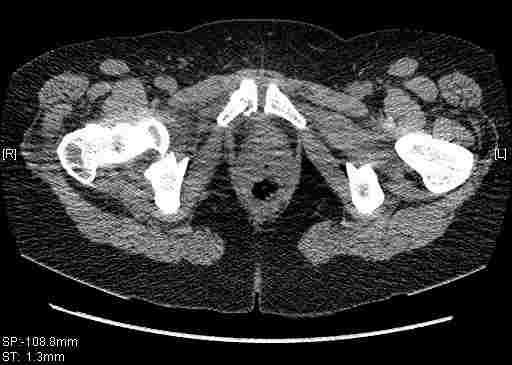

Re: Т-образный перелом вертлужной впадины

Удалось сегодня вывести пациентку в соседнюю больницу, где есть кт. Срезы сделаны только горизонтальные.